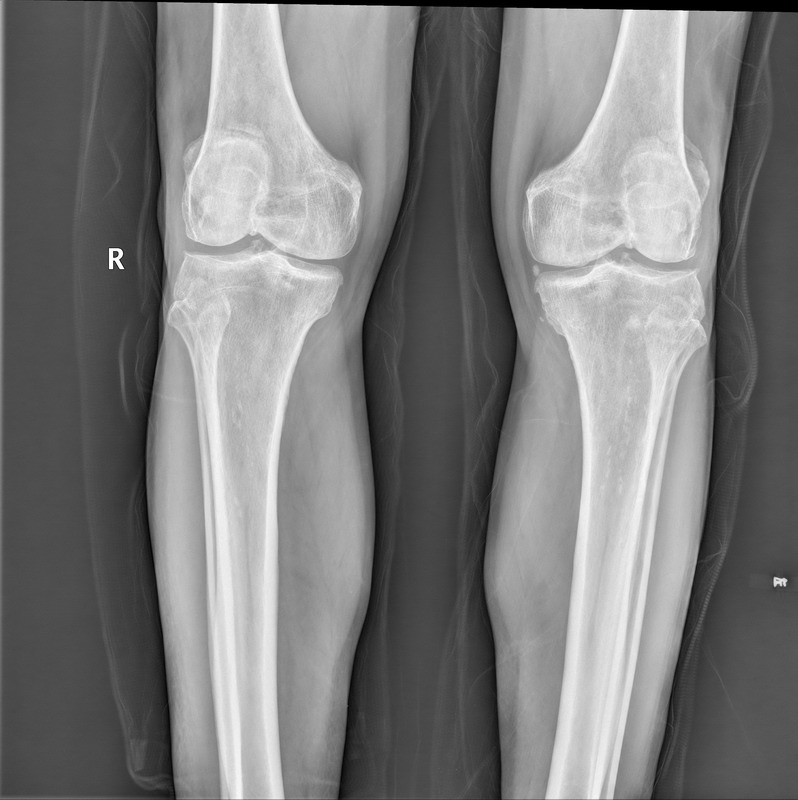

以下是引用yangyudong333在2010-4-12 5:59:00的发言:[br]双膝退变并骨间膜钙化。

以下是引用随光逐影在2010-4-12 8:14:00的发言:[br]1)双膝关节退行性改变。2)双小腿软组织内钙化(骨间膜钙化?血管壁钙化?)。